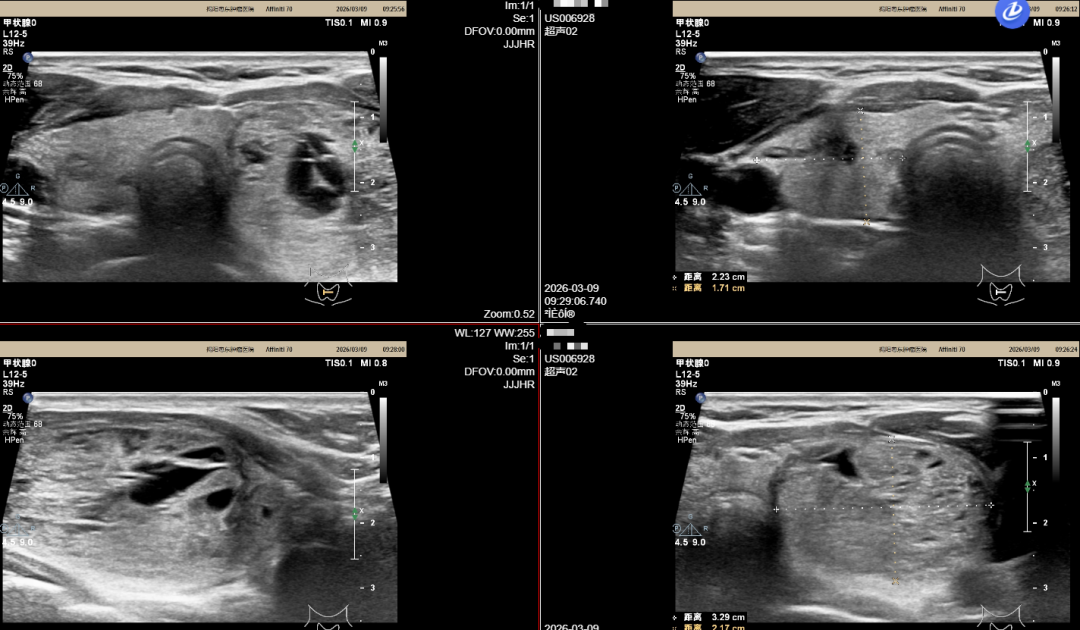

案例三

患者为44岁女性,发现左侧甲状腺肿块1年有余,大小约75px x 87.5px,无声音嘶哑、无饮水呛咳等情况,未予特殊处理。该名患者定期复查甲状腺彩超,甲状腺肿块未见明显增大,现为求进一步治疗来我院就诊。

我院影像学报告提示该名患者甲状腺双侧叶内见多个低回声及混合回声结节,左侧叶较大者大小约39mm x 20mm x 41mm,右侧叶较大者大小约7mm x 6mm。在我院行甲状腺结节微波消融治疗后,患者恢复良好,颈部仅见针尖大小痕迹。